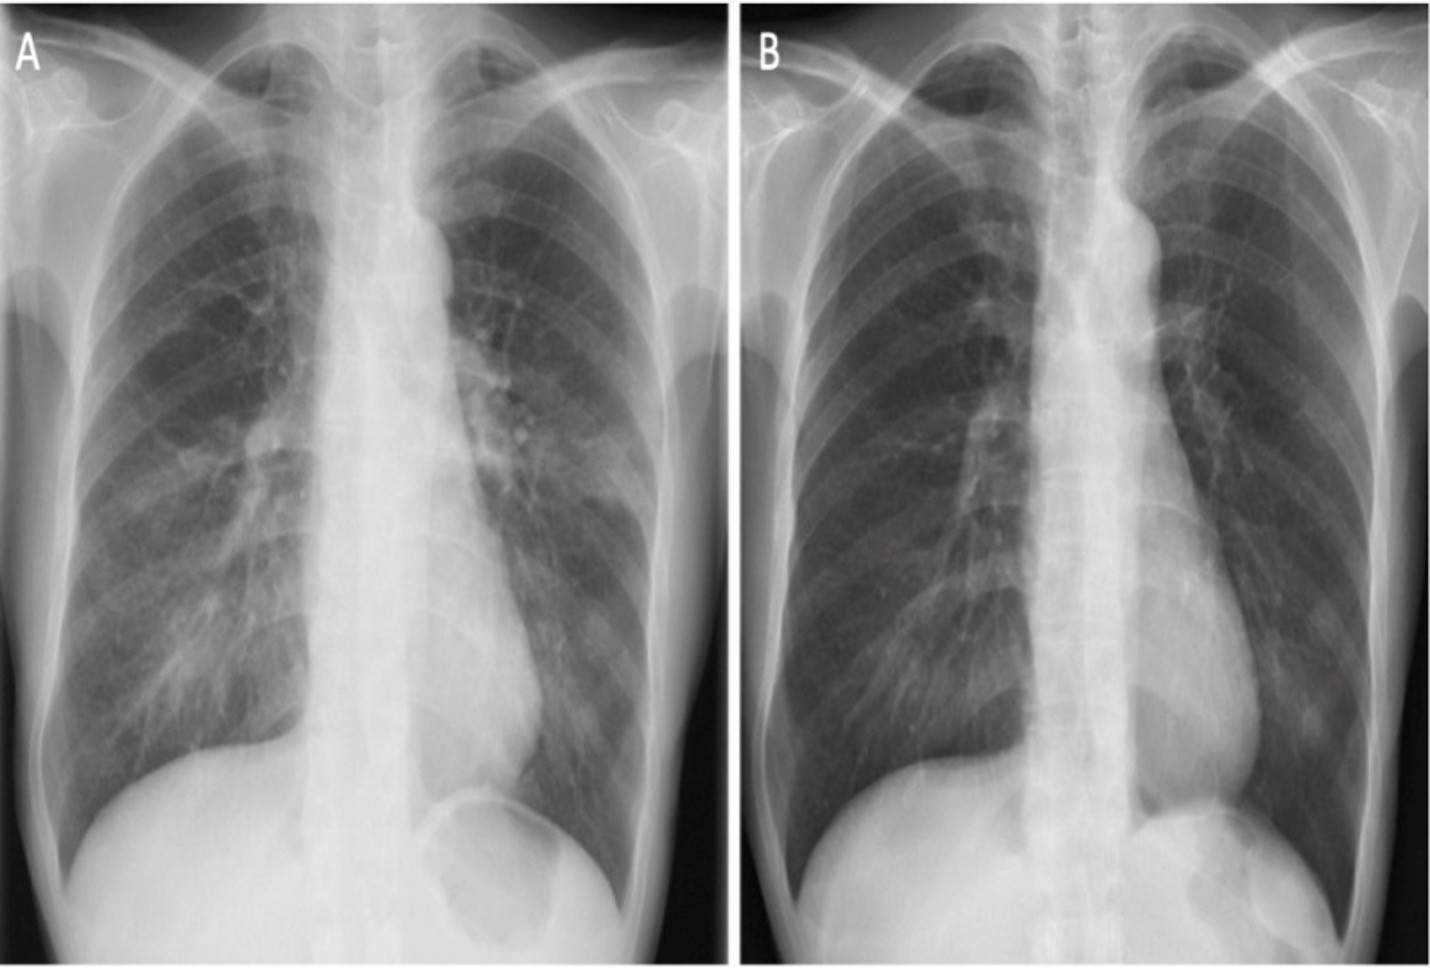

Thứ hai, thuốc lá nung nóng liên quan đến các ca viêm phổi tăng BCAT cấp tính. Bác sĩ Lâm dẫn chứng một ca bệnh là phụ nữ 47 tuổi bị viêm phổi tăng bạch cầu ái toan cấp tính, sau khi chuyển từ hút thuốc lá truyền thống sang sử dụng thuốc lá nung nóng. Bởi các triệu chứng hô hấp ho, sốt nhẹ và các bất thường trên X-quang phổi xảy ra ngay sau khi chuyển đổi thói quen hút thuốc. Tình trạng bệnh nhân được cải thiện sau khi ngừng sử dụng thuốc lá nung nóng và được điều trị bằng corticosteroid.

Thứ 3, thuốc lá nung nóng gây viêm phổi tăng bạch cầu ái toan cấp tính. Về mối nguy hiểm này, bác sĩ Lâm đưa ra một trường hợp thanh niên 16 tuổi bị viêm phổi tăng bạch cầu cấp tính mức độ nặng sau sử dụng thuốc lá nung nóng 2 tuần, với triệu chứng khó thở nặng dần. Bệnh nhân được chuyển đến khoa cấp cứu và được đặt nội khí quản, thở máy, chạy ECMO do suy hô hấp nặng.